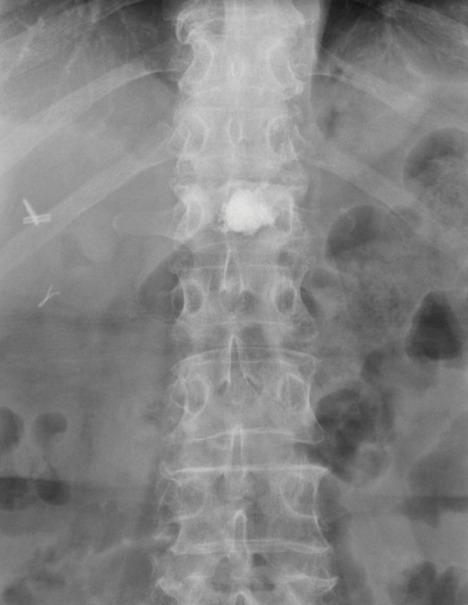

This study includes 22 vertebroplasty procedures performed from October 2018 to July 2020 in 21 patients with traumatic or osteoporotic vertebral fractures (19 female, two men; age between 53 and 89 years). All treatments were executed under fluoroscopic guidance using 11 or 13 G needle through transpedicular or costovertebral unilateral approach. Each patient underwent conscious sedation, continuously monitored by an anesthesiologist. Preoperative MRI images, obtained by 3T or 1.5T MRI scanner, always showed bone marrow edema. The VAS scale and Roland Morris disability questionnaire (RMdq) were administered to patients before and after the treatment to evaluate pain and life quality.

本研究纳入了 2018 年 10 月至 2020 年 7 月期间 21 例创伤性或骨质疏松性椎体骨折患者(19 名女性,2 名男性;年龄 53-89 岁)的 22 例椎体成形术。所有治疗均在透视引导下通过经皮或肋椎关节单侧入路,使用 11 或 13G 针进行。每位患者均在麻醉师的连续监测下接受清醒镇静。术前 MRI 图像由 3T 或 1.5T MRI 扫描仪获得,均显示骨髓水肿。在治疗前后,使用视觉模拟评分(VAS)量表和 Roland Morris 残疾问卷(RMdq)对患者进行疼痛和生活质量评估。